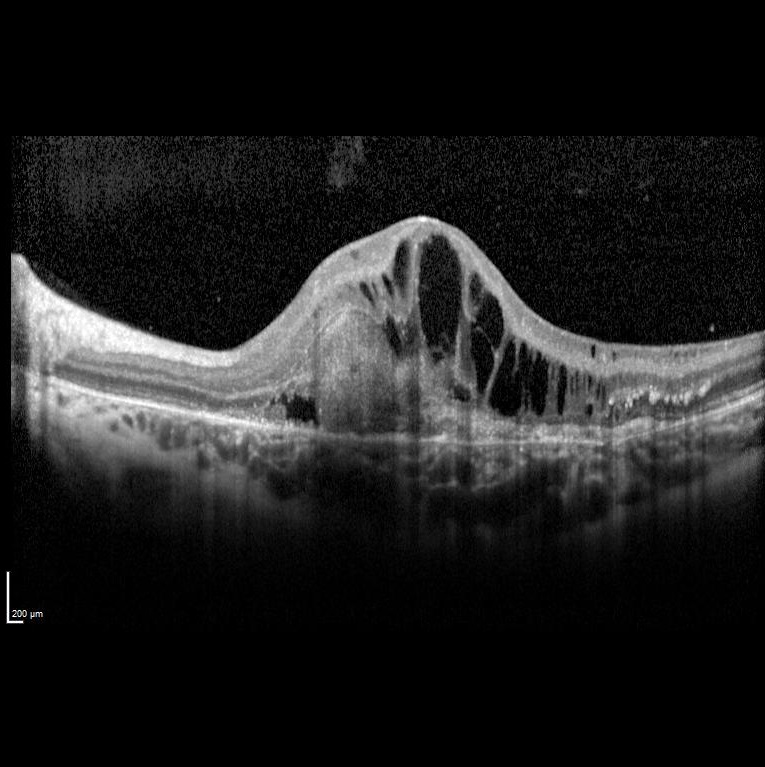

Sol gözde bir haftadır görme azlığı şikayeti başlayan ve görme keskinliği 5 mps düzeyinde olan 15 yaşındaki kadın hasta retina kliniğimize refere edilmiştir. Hastanın renkli fundus ve optik koherens tomografi görüntülerini görmektesiniz. Hastanın doğumunda bir enfeksiyon öyküsü vardır. Sistemik bir hastalığı yoktur. Bu bulgulara göre tanınız nedir? Lütfen cevabınızı aşağıya yazınız.